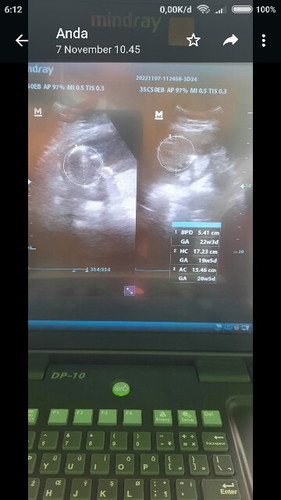

BPD (biparietal diameter) ukuran dr pelipis kiri ke kanan : 5,41 cm menurut hasil BPD GA (gestational age/umur kehamilan) :22 minggu 3 hari HC (head circumferential) itu lingkar kepala janin : 17,23 cm menurut hasil HC usia kehamilannya 19minggu 5 hari AC (abdominal circumferential) itu lingkar perut janin: 15,46 cm menurut hasil AC usia kehamilannya 20 minggu 5 hari kalau bingung usia kehamilannya pake yg mana, itu klo di rata-rata 21 minggu